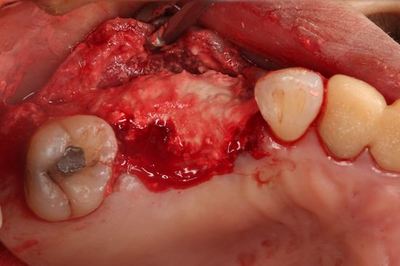

病変の大きな歯の抜歯後に円形の骨欠損があります。

大臼歯部分のインプラント埋入を終えました。

小臼歯部分の骨欠損はCTで確認した通りですので

今回は埋入せず、骨増生処置(GBR)を行います。